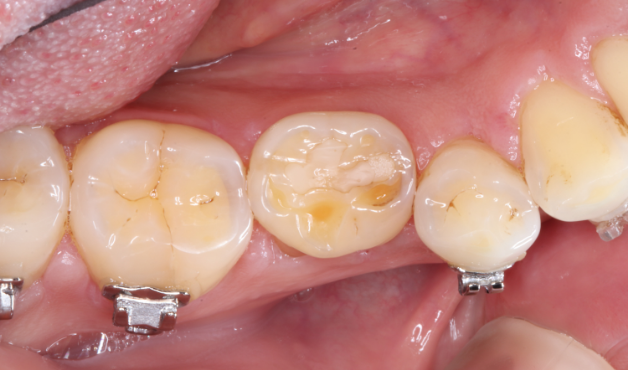

自家歯牙移植と根管治療で

天然歯を保存した症例

タップで写真の拡大ができます。

Before

Under Treatment

After

主訴

歯を残せないと言われた。インプラントは先延ばしにしたい

治療内容

自家歯牙移植 / イニシャルトリートメント(大臼歯)レジンコア

治療期間

2ヶ月

治療費用

308,000

治療の

リスク

術後しばらくしてから骨性癒着、外部吸収を起こす可能性があります。